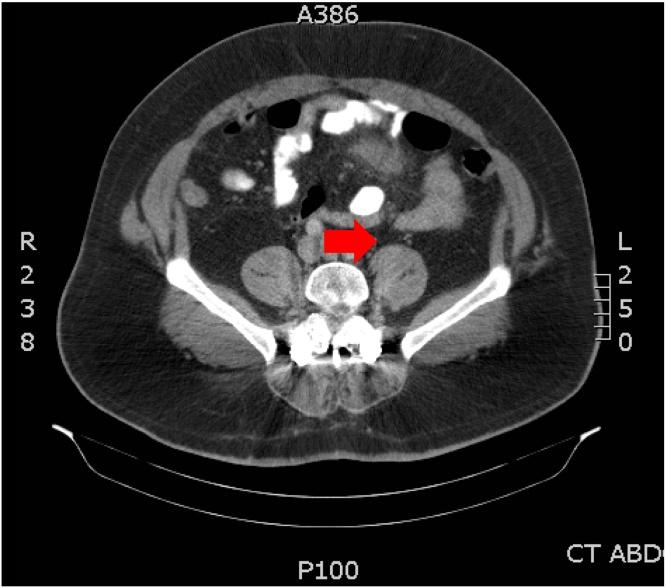

PRESENTATION OF CASE

A 41 year-old male patient presented to an academic teaching hospital with several days of abdominal pain with nausea and vomiting. Initial workup was unremarkable, save for abdominal CT revealing a central mesenteric focus of inflammation. Neuroendocrine tumor was excluded by normal serum octreotide, 5-HIAA, and chromogranin A. A 4×2cm mass was identified and resected on laparoscopy. Histopathologic diagnosis of the specimen was infarcted mesothelial cyst. The patient reported resolution of symptoms and remains well on most recent follow-up.

病例介绍

一名41岁男性患者因数天的腹痛伴恶心、呕吐就诊于一家学术教学医院。初步检查无异常,腹部CT显示肠系膜中央有炎症病灶。血清奥曲肽、5-羟吲哚乙酸和嗜铬粒蛋白A正常排除了神经内分泌肿瘤。通过腹腔镜检查发现并切除了一个4×2cm的肿块。标本的组织病理学诊断为梗死性间皮囊肿。患者报告症状缓解,最近一次随访时情况良好。